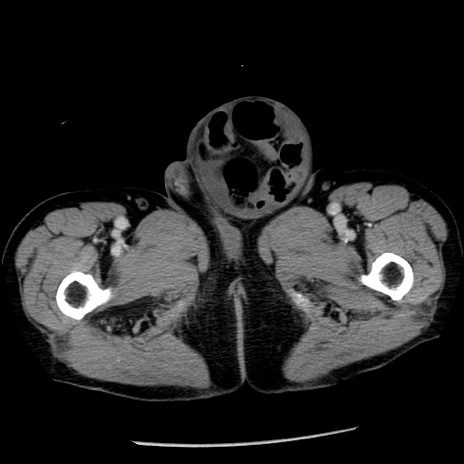

症例26(横断像)

【症例】80歳代男性

【主訴】嘔吐

【現病歴】昨晩2回嘔吐あり、今朝になっても嘔吐あり。来院。

【既往歴】胃潰瘍

【身体所見】意識清明、BT 37.6℃、BP 166/95mmHg、HR 100bpm、SpO2 97%、腹部:平坦・軟、腸蠕動音聴取良好、圧痛なし。

【データ】WBC 21900、CRP 1.46